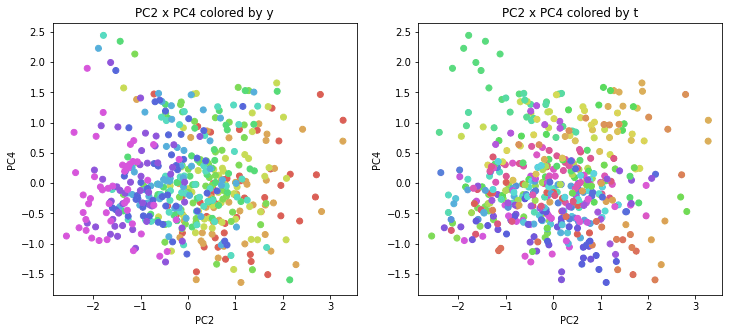

PCAの結果の第n主成分をPCnと表記します。

医療費データの場合と同様に、PCAの結果を見やすく表示するため、seabornのカラーパレットを使って、年月別、都道府県別に色分けして図示してみます(左側が年月別に色分け、右側が都道府県別に色分け)。PC1~PC8まで表示しました。

医療費データの場合ほどはっきりとはしていませんが、PC2が概ね時間の経過を表す成分で、残りの成分が時点によって変わらない地域の特徴を表す成分となっているようです。

また、PC1×PC3を見ると、47沖縄が他の都道府県からかなり離れたところに位置しており、沖縄の地域差が際立っているのが分かります。これは、以前別の記事で年齢階級のない健診データでPCAを実行した場合と似た結果となっています。

今回は、医療費データと同様に、健診データ240次元についてPCAを実行してみました。PCAの結果、医療費データの場合ほどはっきりしとはしていませんが、第2主成分が概ね時間の経過を表す成分で、時間軸に沿った全体的な動き(全国的な動き)を表しており、それ以外の成分が地域の特徴を表す成分で、この10年間あまり変わっていないことがわかりました。